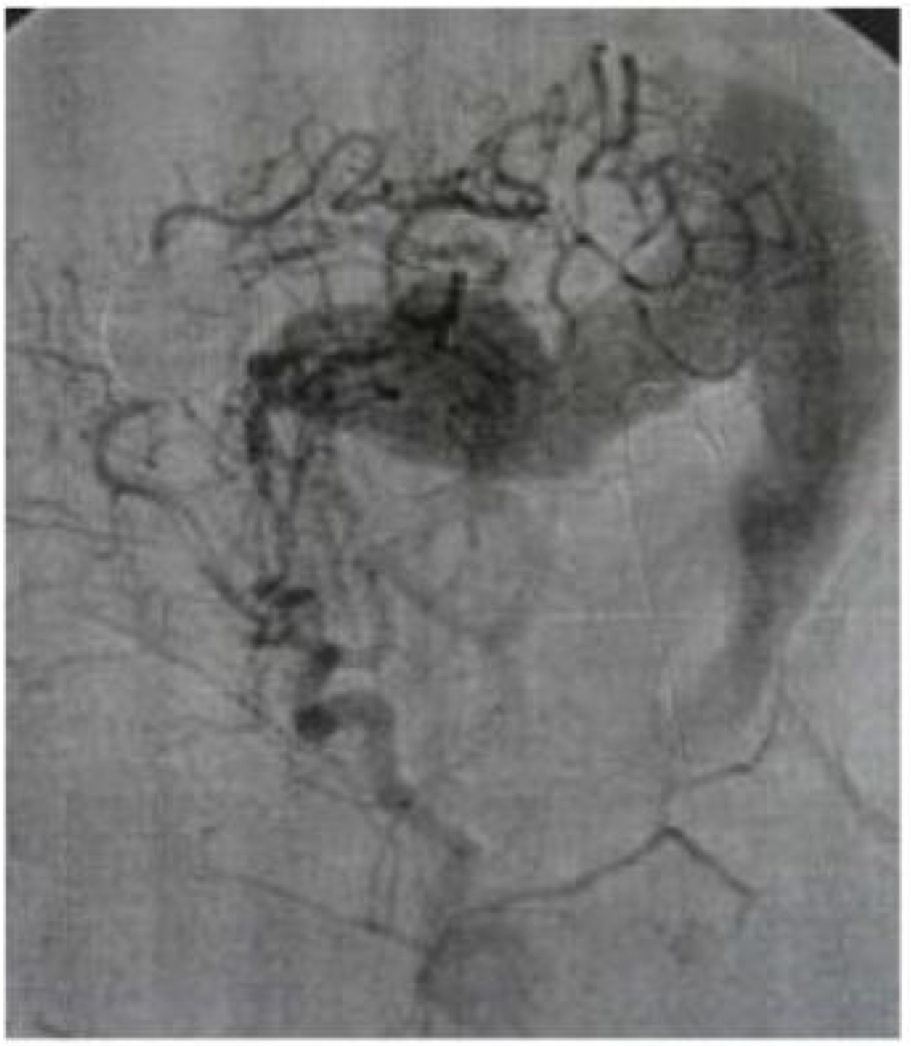

Gambar di bawah ini menunjukkan penyakit ?

A. AVM

B. Carotid Occlusion

C. Dural AVM

D. Meningioma

E. Moyamoya disease

D

Pengobatan terbaik pada pasien dengan kejadian iskemia multipel dan ditampilkan dengan angiogram yaitu?

A. Carotid endarterectomy

B. Encephalomyosynangiosis

C. Heparinization

D. Superficial temporal artery to middle cerebral artery bypass

E. no treatment

C